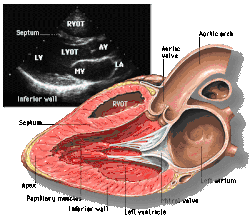

Parasternal long axis (PLAX)

This view is obtained to the left of the sternum and views the heart in its long axis. In this view, the mitral valve, aortic valve, right ventricular outflow tract, base of the left ventricle, and the left atrium can be visible. Angulation in this view can bring the right ventricular inflow tract and tricuspid valve into view, and angulation the opposite way can bring the pulmonary valve into view.

In this view, it is possible to appreciate the long-axis cross section of the mitral and aortic valves. The classic "hockey stick" shape of rheumatic mitral stenosis can be appreciated in this view. However, the angle of the probe with these valves can lead to under-appreciation of valve dysfunction.

The parasternal long view of the pulmonary valve is the only view of the posterior leaflet.

Structures visible:

- Anterior septal and inferior lateral walls of the left ventricle

- Left atrium

- Mitral valve in long-axis with chordae

- Aortic valve in long-axis

- Tricuspid valve in long-axis (angulated) and right ventricular inflow tract

- Pulmonary valve in long-axis (angulated) and right ventricular outflow tract

Measurements in this view can be used to quantify the heart:

- Left ventricular size and wall thickness

- Left atrial linear dimension (as opposed to area)

- Left ventricular outflow tract diameter (used to calculate aortic valve area by the continuity equation)

- Aortic annulus, sinus of Valsalva, and aortic root sizes

- Color doppler of all four valves

- Spectral doppler of tricuspid and pulmonary valves